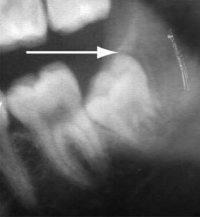

Segment of an orthopantomogram showing an impacted wisdom tooth: a radiolucent area (arrow) is seen behind an impacted right lower wisdom tooth from a patient with pericoronitis.

A 35-year-old man presented to a hospital emergency department with severe pain of 2 days’ duration originating in the left lower jaw and radiating into the temporal area. The pain was described as sharp and shooting in nature; it was present all the time and not relieved by paracetamol + codeine. Complete general and local physical examination performed at the emergency department did not reveal any obvious cause of the pain. A diagnosis of trigeminal neuralgia was made by exclusion, and the patient was prescribed 200 mg carbamazepine twice a day and advised to consult his GP during the week. The patient presented 32 hours later complaining of excruciating pain, despite having taken three carbamazepine tablets.

On examination of the oral cavity, a partially erupted left lower molar was noted, with surrounding mucosal erythema and extreme tenderness of the surrounding gum (see image in this Box). A diagnosis of pericoronitis was made.

Ideal management: Pericoronitis should be treated by irrigation of the pericoronal space with a sterile solution such as saline or 0.12% chlorhexidine. Broad spectrum antibiotics should be given if there are systemic symptoms.7,8 The patient should be referred to an oral and maxillofacial surgeon/dentist for surgical extraction of the tooth.